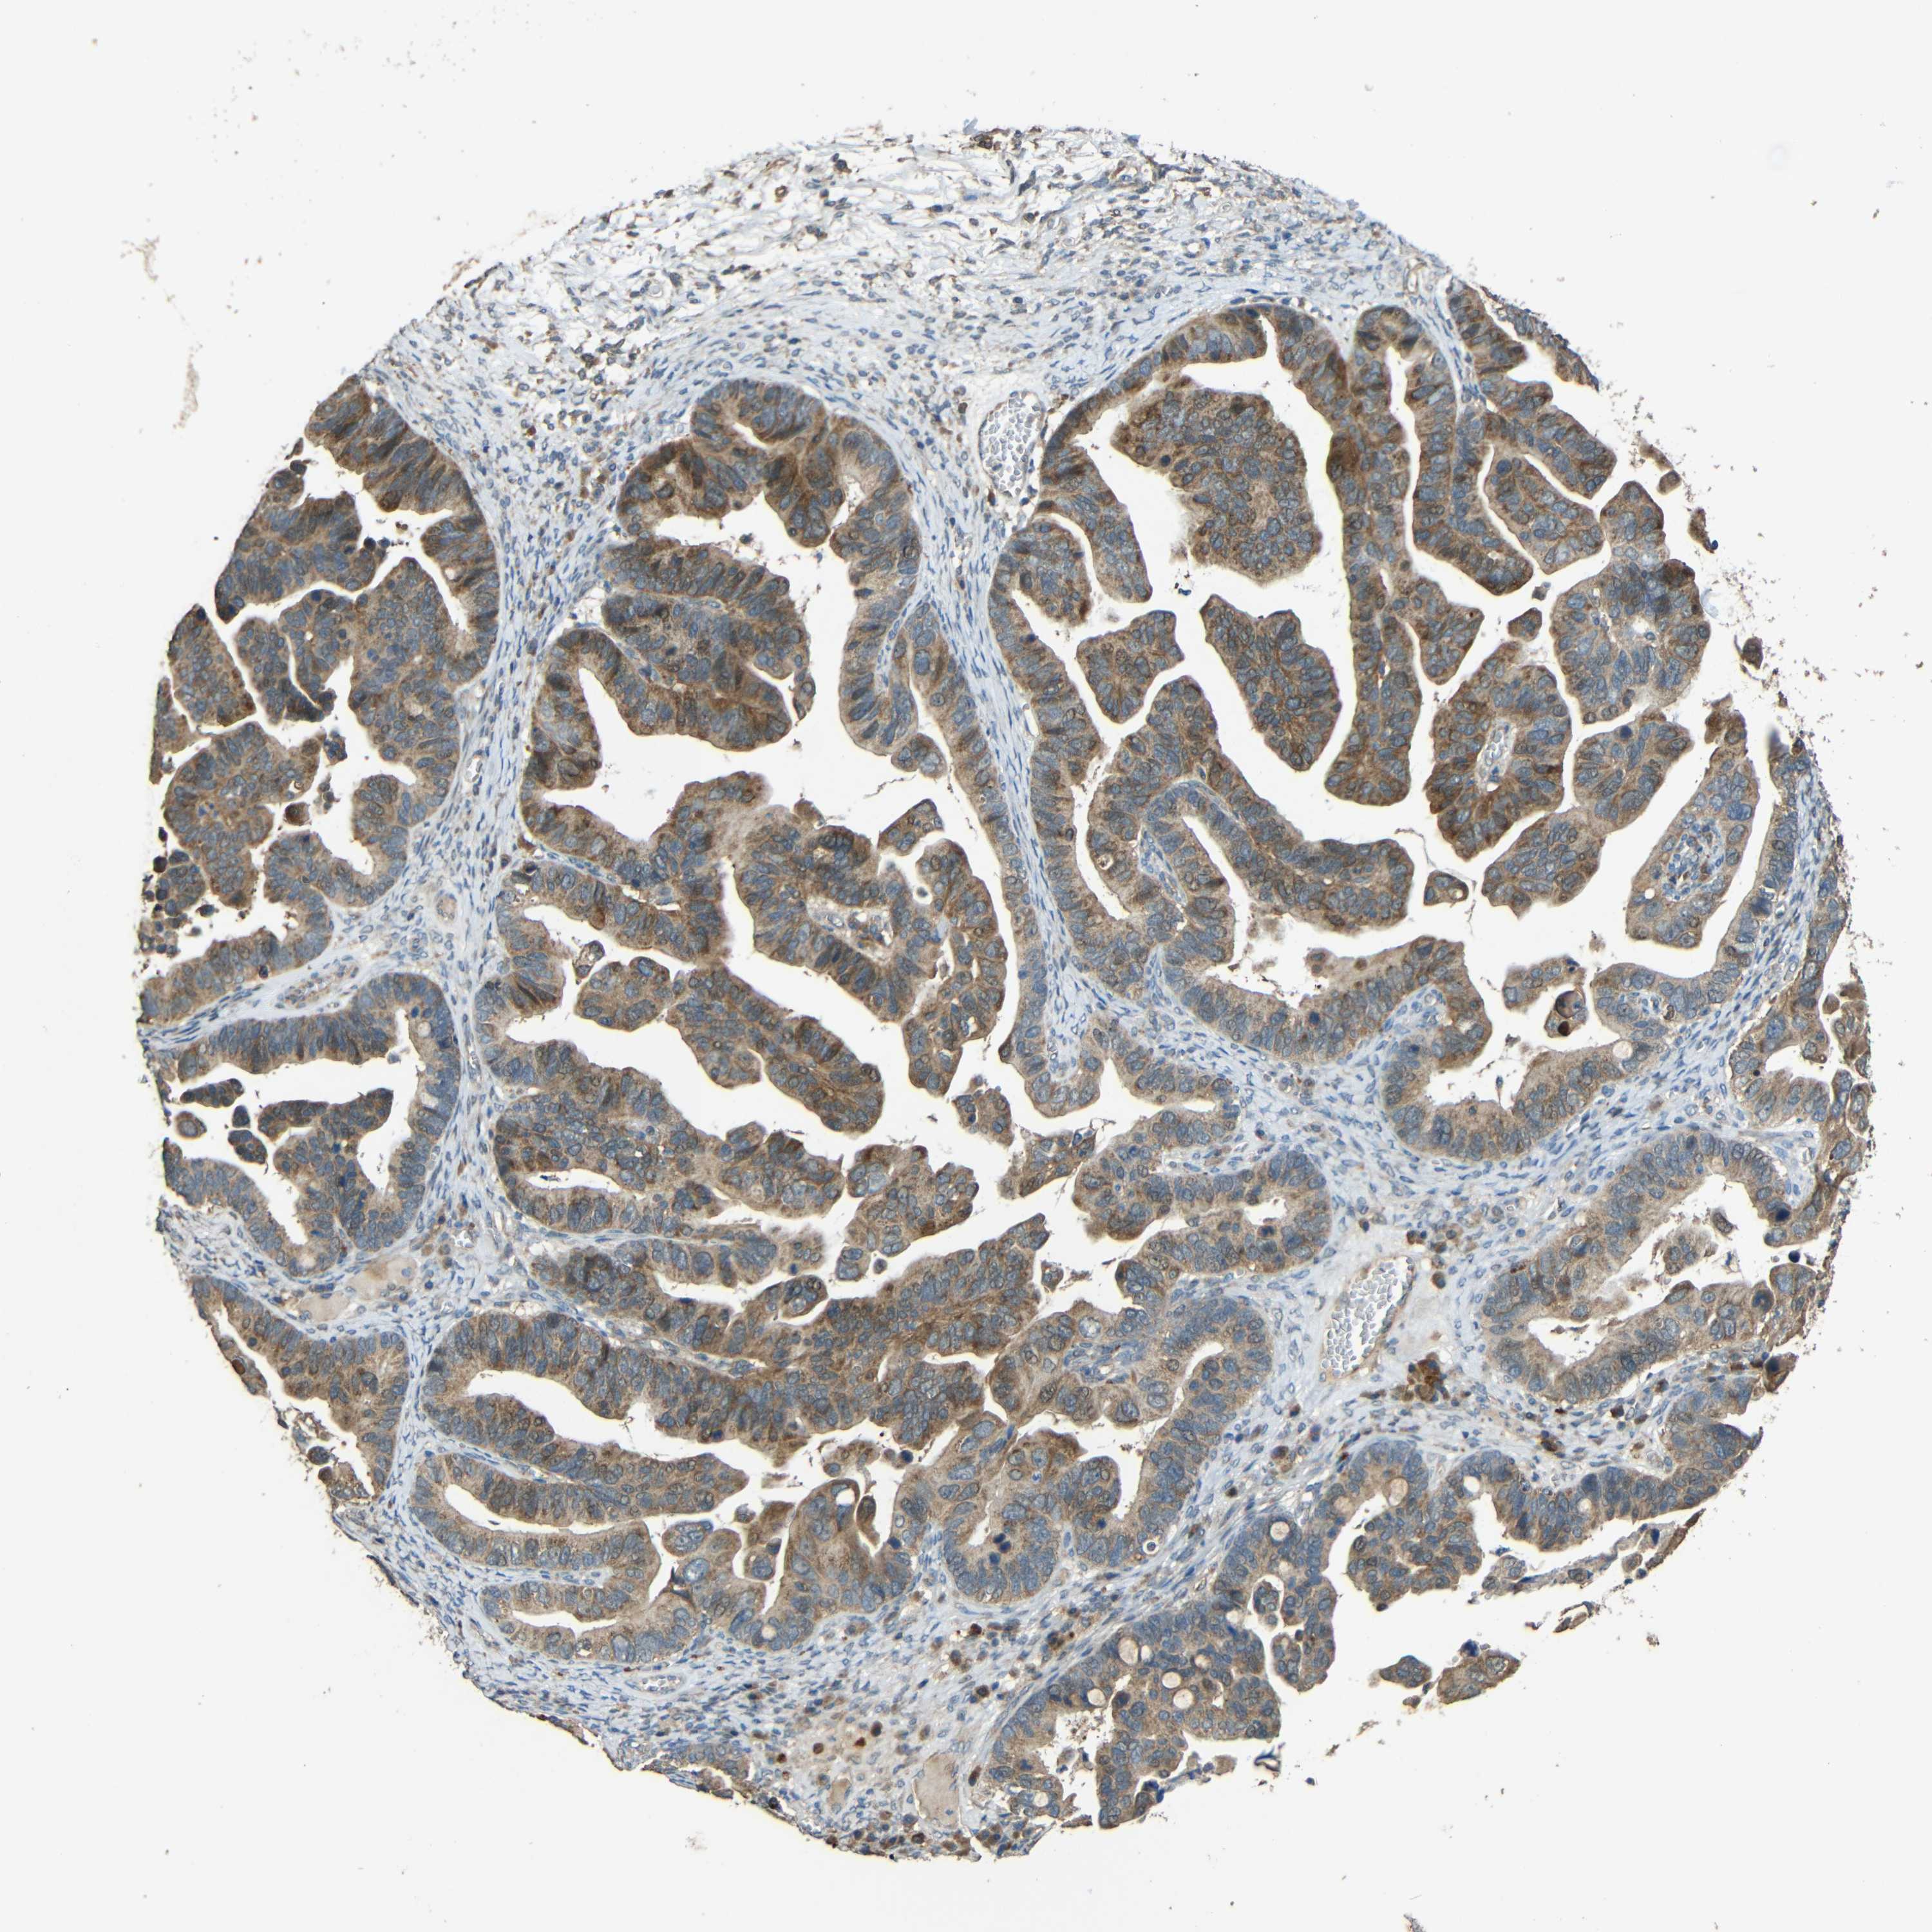

OVARIAN CANCER - Protein expressioni

A mouse-over function shows sample information and annotation data. Click on an image to view it in a full screen mode. Samples can be filtered based on level of antibody staining by selecting one or several of the following categories: high, medium, low and not detected. The assay and annotation is described here.

Note that samples used for immunohistochemistry by the Human Protein Atlas do not correspond to samples in the TCGA dataset.

Antibody stainingi

Antibody staining in the annotated cell types in the current human tissue is reported as not detected, low, medium, or high, based on conventional immunohistochemistry profiling in selected tissues. This score is based on the combination of the staining intensity and fraction of stained cells.

Each image is clickable and will lead to virtual microscopy that enables deeper exploration of all samples and also displays staining intensity scores, fraction scores and subcellular localization as well as patient and tissue information for each sample.

Antibody HPA063018

Antibody CAB013715

Staining

High

Medium

Low

Not detected

Intensity

Strong

Moderate

Weak

Negative

Quantity

>75%

75%-25%

<25%

None

Location

Nuclear

Cytoplasmic/membranous

Cytoplasmic/membranous,nuclear

Cystadenocarcinoma, serous, NOS

Cystadenocarcinoma, mucinous, NOS

Carcinoma, endometroid

Carcinoma, NOS